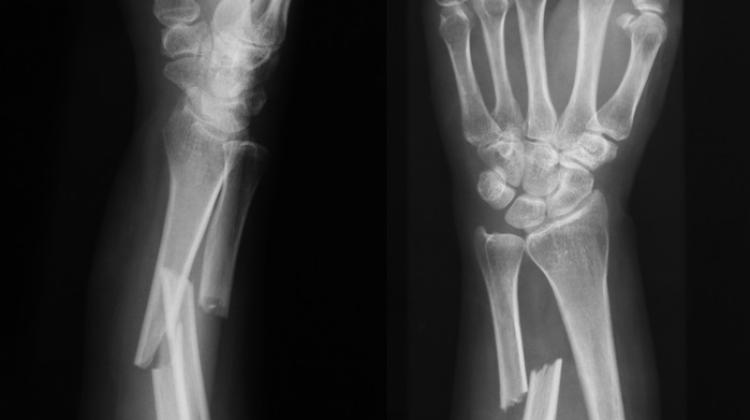

Ученый работает над биоматериалом из нановолокон, который можно будет вводить непосредственно в место перелома. В конечном итоге это поможет пациентам, чьи кости срастаются слишком медленно или когда этому процессу препятствуют проблемы, связанные, среди прочего: с остеопорозом.

Доктор Лукаш Шиманский из Института генетики животных и биотехнологии Польской академии наук работает над созданием наноструктурированных полимерных каркасов для поддержки регенерации костей. Ученый – победитель конкурса NCBR LIDER, его командный проект получит максимальное запланированное финансирование – 1,8 млн злотых. Как объяснил Nauka w Polsce доктор Шиманский, костные заменители, изготовленные из недавно разработанного биоматериала, будут помещаться в щель перелома с помощью шприца. Биоматериал увеличит клеточную и молекулярную активность, облегчая транспорт питательных веществ в ткани. Полужидкая форма биоматериала позволит ему оставаться в месте имплантации. ПИТАНИЕ ДЛЯ РЕГЕНЕРАЦИИ КОСТЕЙ В рамках научного проекта под руководством доктора Шиманского исследователи создают экологически чистые каркасы из нановолокон. Процесс их создания предполагает технику электропрядения. Каркасы содержат выбранные пептиды. Они стимулируют рост и регенерацию костей, помогая строить новые ткани. Они также содержат аминокислоты, которые помогают в процессе заживления костей за счет выработки коллагена. Вспомогательные вещества высвобождаются при воздействии на биоматериал электромагнитного излучения. Кроме того, к поверхности нановолокон прикреплены наночастицы серебра, которые предотвращают рост бактерий и способствуют образованию кровеносных сосудов. Доктор Шимански называет четыре основных преимущества материала. «Прежде всего, он будет передавать специальные сигналы, которые помогут стволовым клеткам двигаться и заселять место перелома. Нановолокна в материале создадут поры, через которые питательным веществам будет легче проникать. Биоматериал будет работать таким образом, чтобы стимулировать процесс заживления костей, а также быть простым в использовании, что облегчит работу ортопедов, хирургов и медицинского персонала", - перечисляет он. фото из архива Лукаша Шиманского ЭФФЕКТИВНОЕ ЛЕЧЕНИЕ ПЕРЕЛОМОВ Как подчеркивает руководитель, современные методы лечения переломов являются дорогостоящими и трудоемкими. В наиболее сложных случаях отсроченного сращения применяют следующие методы: вводятся костные трансплантаты, имплантация каркаса, а также вещества, стимулирующие рост костной ткани. Эти процедуры часто требуют хирургического вмешательства, которое несет в себе риск осложнений, таких как кровотечение и инфекция. Терапия стволовыми клетками находится в стадии разработки, и, по словам доктора Шиманского, новый биоматериал может способствовать созданию новых методов доставки таких клеток к месту перелома. Это также может принести многочисленные преимущества в области челюстно-лицевой хирургии и стоматологии. Материал предназначен для удовлетворения потребностей людей, кости которых срастаются слишком медленно или не срастаются вообще. Проблемы с задержкой сращения костей затрагивают 5-10 процентов. люди с травмами, особенно с переломами бедренной кости и большеберцовой кости, например, в результате автомобильных аварий. Возраст пациента связан с риском – чем старше пациент, тем больше риск осложнений при лечении переломов, особенно у людей с остеопорозом. Среди более молодых пациентов переломы костей чаще всего возникают в результате спортивных травм, падений с высоты и, что становится все более проблематичным для систем здравоохранения во всем мире, дорожно-транспортных происшествий. Наука в Польше, Каролина Душчик кол/зан/